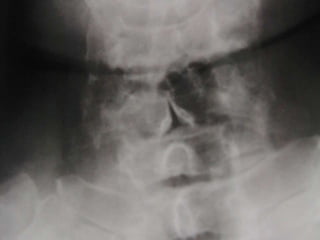

AP Columna Lumbar

Estructuras Visualizadas

•Cuerpos vertebrales L1-L5

•Pediculos

•PE's

•Lamina

•PT's

•Base Sacral

•Sombra del Psoas

AP Columna Lumbar -

Marcado